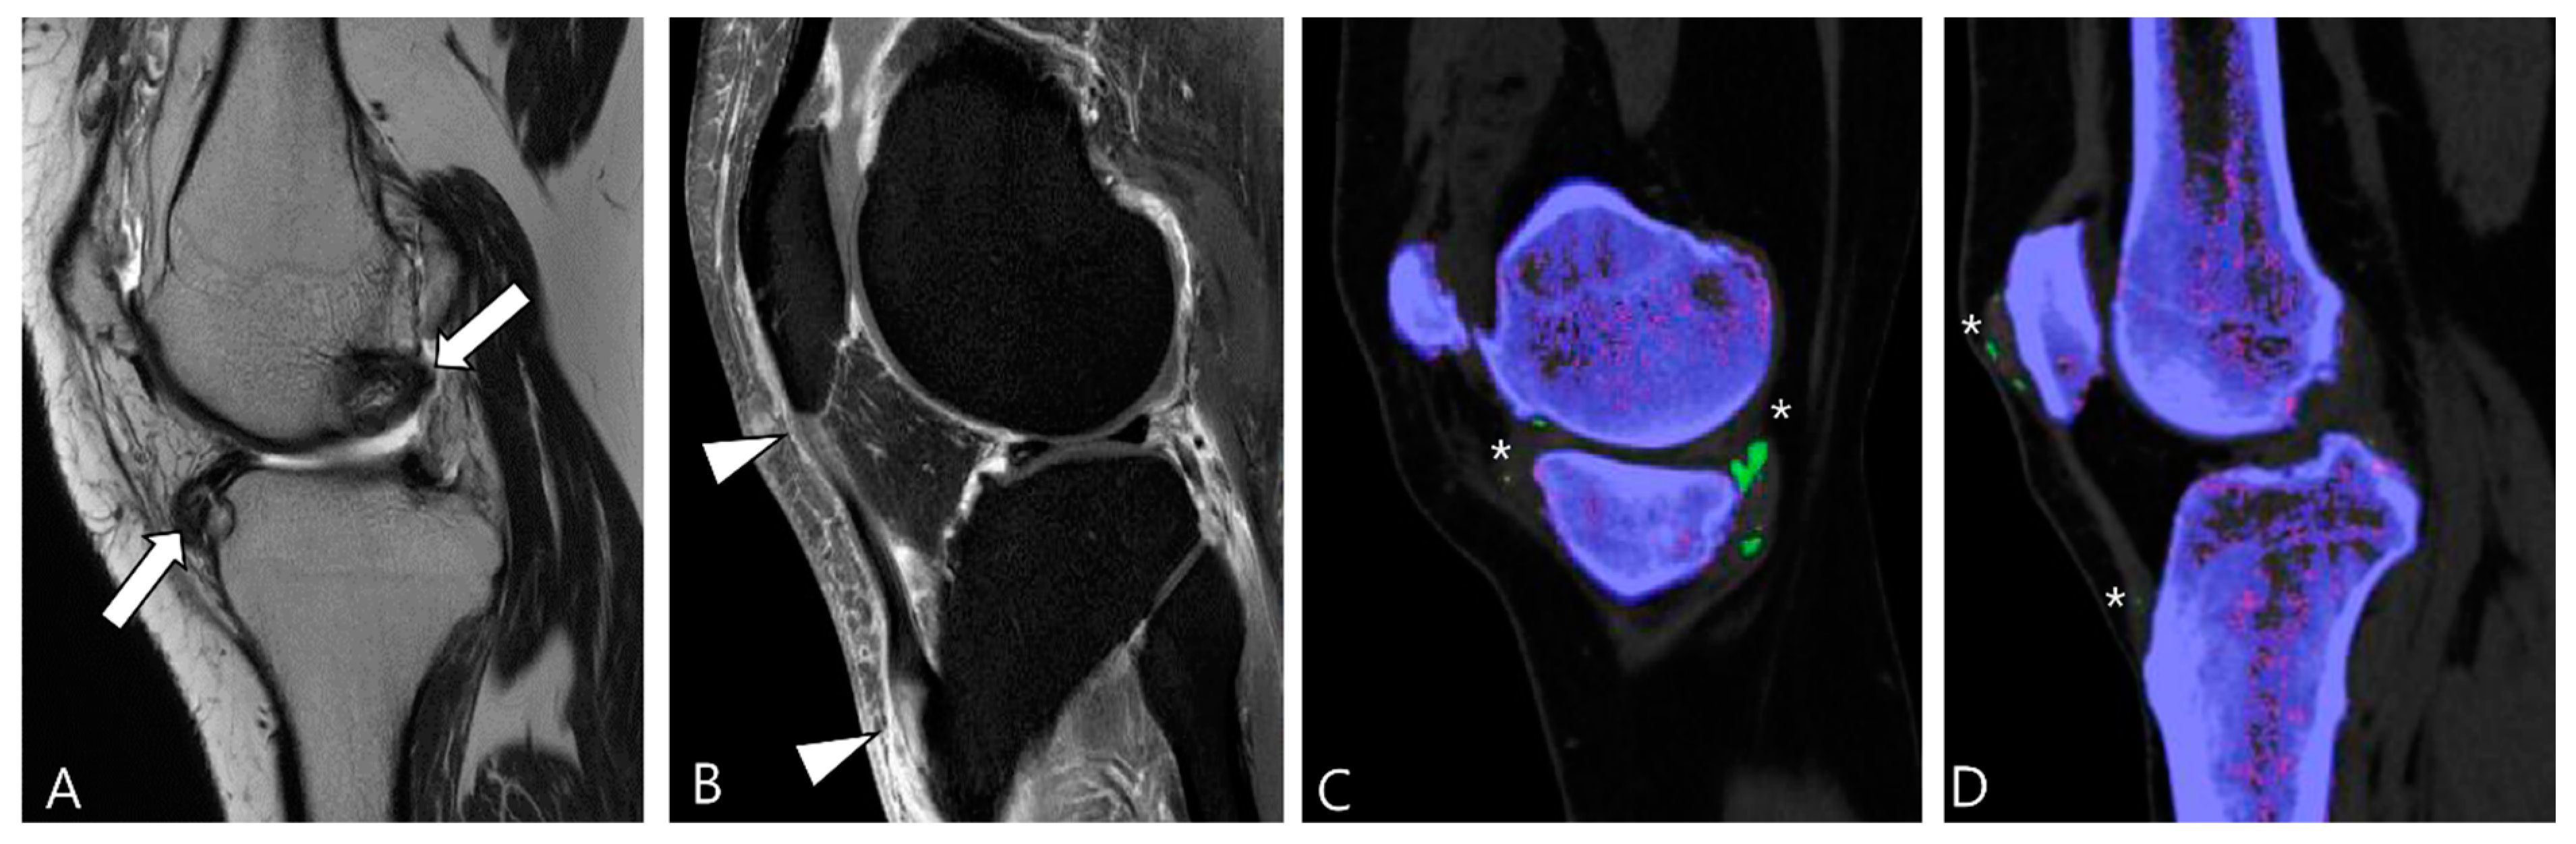

2.3. Morphological Findings for D-TSGCT

2.4. Relationship to Adjacent Structures of D-TSGCT

2.5. Advanced MRI Sequences for D-TSGCT

3.1.5. Tophaceous Gout

3.2.3. Tophaceous Gout